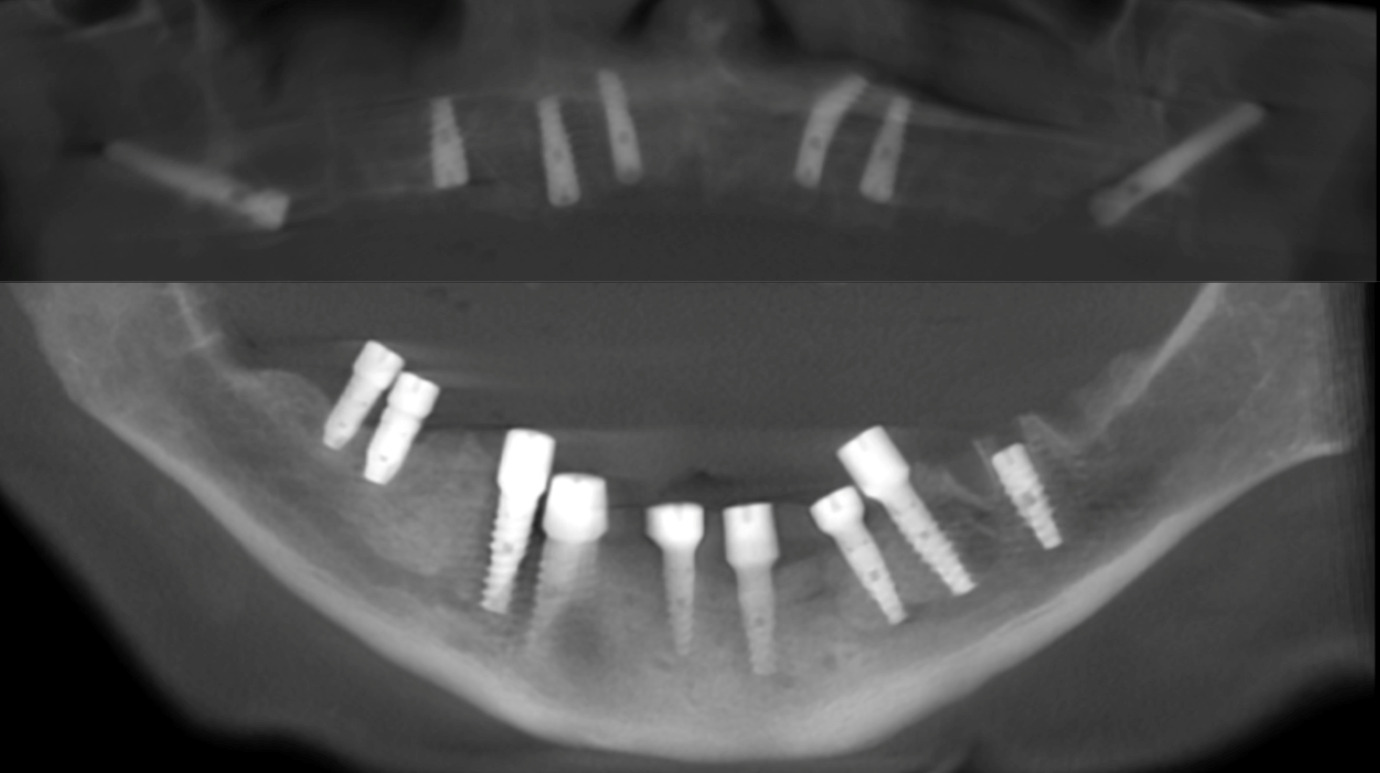

Мы перерассчитали геометрию челюсти, заново расставили нагрузки на импланты и выбрали места и оси так, чтобы они дальше обеспечили максимально физиологичное положение зубов. Это очень нестандартная процедура, поскольку при такой анатомии челюстей после травм стандартные протоколы не подходят, стандартный софт тоже не всегда подходит, и нужно поковыряться с нашими проектировочными решениями. Достаточной квалификацией для эстетичного и при этом правильно учитывающего нагрузки (то есть долговременного) решения в России обладает чуть больше десятка специалистов, из которых половина в Москве.

Дальше мы начали крепить импланты, то есть вворачивать винты в челюсть, которые далее станут слотами для конструкций, замещающих коронки зубов (те части зубов, что выше челюсти). Импланты работают новыми корнями и ставятся частично в новую кость.

Импланты поставили